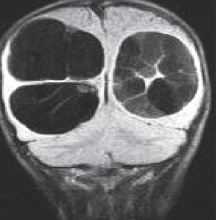

Атрофией считается уменьшение передне-заднего измерения спинного мозга по результатам МРТ меньше 7 мм в шейном отделе и меньше 6 мм в грудном. Участок атрофии при МРТ может быть локальным или протяжённым, если он распространяется более чем на 2 позвонковых сегмента. Граница атрофии на Т2-взвешенных МРТ нечёткая. Распространённая атрофия является типичным отдалённым последствием спинальной травмы.

МРТ шейного отдела позвоночника. Компрессия и атрофия спинного мозга. Т2-взвешенная сагиттальная МРТ.